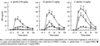

What evidence shows that a combination of Ghrelin and GHRH elicits a larger release of GH synergistically

Because of the two different mechanisms achieving the same goal, there is scope for large amplification when combined